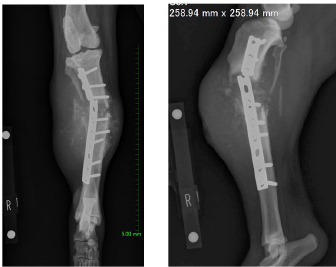

AbstractBackground: There are few detailed reports on implant-associated sarcoma in dogs; however, loose implants, metal type, and infection have not been shown as specific risk factors for this condition. Case Description: A 14-year-old spayed female Labrador retriever was referred to our hospital with a main complaint of chronic right hind lameness after previous tibial fracture repair. On radiographs, rupture of the bone plate and screws with swelling of the surrounding soft tissue was observed, and osteosarcoma (OSA) was diagnosed after histopathological examinations. During amputation surgery, a plastic band was found associated with the implant. Conclusion: Veterinary surgeons should be aware of implant-associated OSA and refrain from using non-medical materials in the implants. Furthermore, they should recommend the removal of orthopedic implants after fracture repair. Keywords: Dogs, Fracture, Implant, Osteosarcoma, Repair. IntroductionOsteosarcoma (OSA) is a highly aggressive mesenchymal tumor that comprises at least 85% of canine bone tumors (Egenvall et al., 2007) and tends to occur in larger individuals, and the most common site in dogs is in the appendicular skeleton near metaphyses (Morello et al., 2011). Several studies have suggested that OSAs result from abnormalities in osteoblast differentiation, as mesenchymal stem cells differentiate through osteoprogenitor and osteoblast phases before becoming mature osteocytes (Tang et al., 2008). Osteoblastic features are common in OSA, suggesting that early disruption of osteogenic differentiation may occur during sarcoma development (Tang et al., 2008). Furthermore, this process is sometimes initiated by the presence of orthopedic implants (Murphy et al., 1997; Rose et al., 2005). Loose implants, metal type, and infection have not been shown to be specific risk factors of implant-associated sarcoma (Sinibaldi et al., 1976; Kenecht et al., 1978; MacDonald et al., 2012). There have been a few reports on implant-associated sarcoma in dogs, albeit with minimal information (Burton et al., 2015; Arthur et al., 2016). Our case describes canine implant-associated OSA at the site of a previous fracture, repaired with bone plate and screws and an unknown plastic band. Case DetailsA 14-year-old spayed female Labrador retriever weighing 21.3 kg was referred to our hospital with a main complaint of chronic right-hind lameness. This patient had undergone surgery for right tibial fracture repair with implantation of bone plate and screws at a referral hospital 12 years ago. The patient showed no appetite, was not drinking, and was lethargic, with a body condition score of 1/5. The patient was unable to stand up on her own, her right hind limb was mostly weak, and she was unable to move independently using her left side. The patient’s state of consciousness was normal. On physical examination, her vital signs were normal (temperature: 38.1°C, pulse 104 beats/minutes with no heart murmur, respiratory rate with normal lung sounds: 32 beats/minutes). The mucous membrane showed a pale color because of severe anemia (packed cell volume 20.4%). In addition, the capillary refill time was delayed by <3 seconds, suggesting severe dehydration. The patient showed swelling and was warm to the touch from the right tibia to the femur, with a swollen right popliteal lymph node, which presented with a ruptured mass lesion approximately 7 × 10 cm in size. The thoracic radiograph was normal (Fig. 1). However, the right hind limb radiograph showed an osteolytic lesion accompanying the ruptured implant and loosening of the plate and screws, with surrounding soft tissue swelling (Fig. 2). Fine needle aspiration from this site suggested OSA (data not shown). Although we could not perform angiographic computed tomography because of the owner’s dissent, we performed amputation from the hip joint on the same day. Gross morphology showed severe inflammation surrounding soft tissues, the rupture of the stainless-steel bone plate, and we noted a non-medical band at the right tibia (Fig. 3). The patient was formally diagnosed with OSA after histopathological examinations (Fig. 4). After 24 hours hospitalization, we administered ampicillin potassium (20 mg/kg, BID) intravenously and prednisolone (0.5 mg/kg, SID) subcutaneously for postoperative care. Also, 24 hours continuous rate infusion of fentanyl (5 μg/kg/minutes) in lactated Ringer’s solution was used for analgesia. The patient was discharged to the owner the day after surgery for home care. The owner refused postoperative radiation therapy and chemotherapy. Unfortunately, this patient died 1 month after amputation.

No metastasis was observed. Fig. 2. Limb radiographs. The right tibia showed an osteolytic lesion with rupture of orthopedic plate, loosening of screws, and also soft tissue swelling. DiscussionOrthopedic implants are commonly used in small animal patients, including dogs, and hence an awareness of potentially serious complications is important. In a study of more than 19,000 open fracture restoration cases in canines occurring between 1970 and 2000, only 15 cases of OSA had occurred at the site of fracture restoration. In other words, the incidence of OSA at a fracture site was less than 0.08% (Arthur et al., 2016). Although long-term inflammation is recognized as a contributing factor to creating an environment promoting tumorigenesis, this relationship has not been demonstrated in reports of implant-associated malignancy. While the effects of implant composition and wear have received great attention, the role of chronic inflammation in the development of sarcoma remains a point of interest (Visuri et al., 2006). Many initiating factors have been hypothesized to play a role in the development of implant-associated sarcoma. Researchers have shown that many implant materials, including commonly used stainless steel and titanium, have potentially carcinogenic properties (Kirkpatrick et al., 2000). Consequently, some surgeons suggest the removal of orthopedic implants after fracture repair. In our case, non-medical bands had been used to surround the bone plate, probably leading to severe inflammation and resulting in the occurrence of OSA at the fracture site. In veterinary medicine, there are few reports about canine implant-associated neoplasia (Burton et al., 2015; Arthur et al., 2016). In a retrospective study of 16 cases of canine implant-associated tumors, it was determined that tumors developed an average of 5.5 years after implant placement. In addition, the hind limbs [tibia (8/16) and femur (5/16)] were favored; 15 of the 16 cases developed in the bone trunk and 13 were OSAs (Burton et al., 2015). Our case showed the same features as those documented in the previous report (Burton et al., 2015).